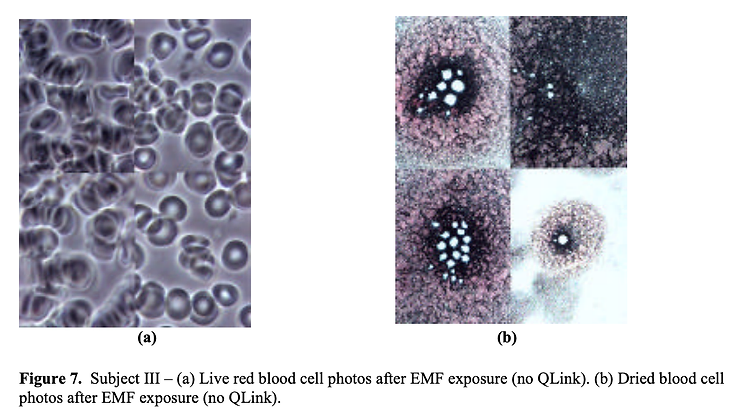

4-subject study Live blood analysis [1.2.3.4] involves visual examination of freshly-drawn capillary blood of subjects that is put between a glass cover slip and microscope slide and viewed using an optical microscope with video enhancement. It shows images of the various types of blood cells in their native state and plasma bodies as small as chylomicrons. It is regarded as an important assessment of the biological terrain of the body by holistic health practitioners.

The test requires either a dark-field or phase-contrast microscope and a high contrast videocamera attached to it. The magnification with video enhancement and projection on a monitor ranges up to 20,000X.

Without EMF Protection

With EMF Protection